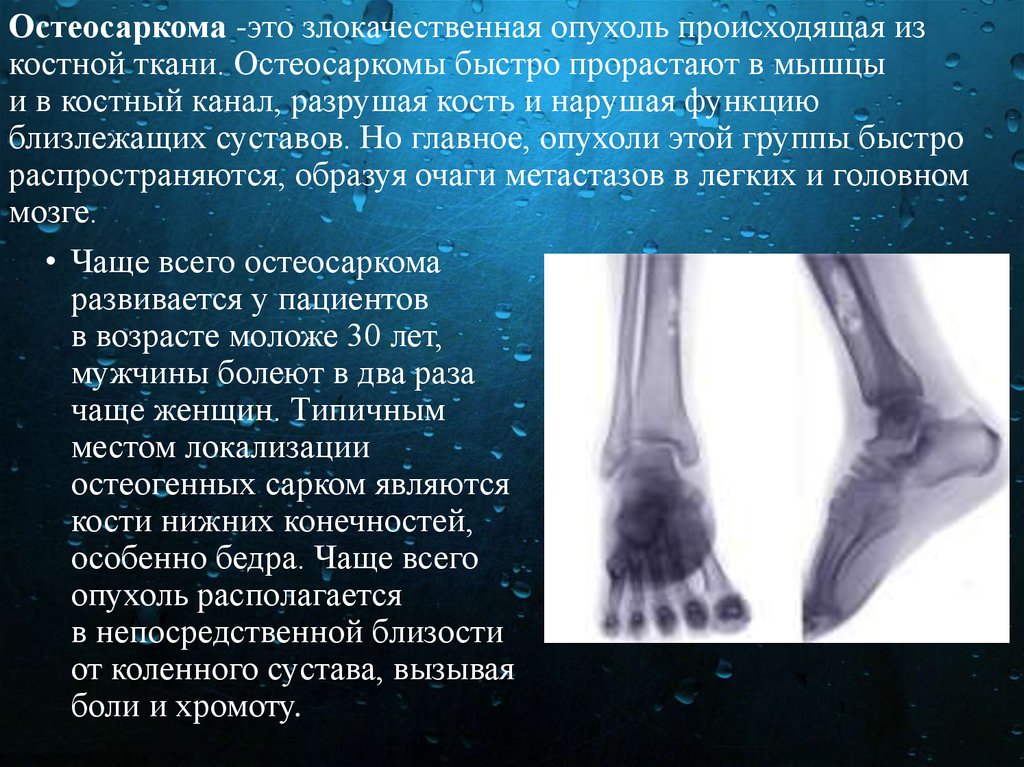

Рентгенологическая картина остеогенной саркомы кости - 98 фото